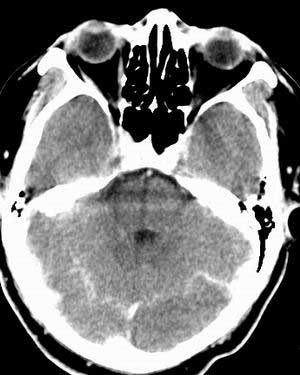

增强扫描:

平扫右侧岩骨与枕骨交角内侧脑质内见淡片状密度增高影,内缘清晰。增强图象上未见明显显示。

考虑:1)伪影可能,建议复查头ct平扫。

2)加照头ct骨窗,以显示乳突气房内是否有病变。